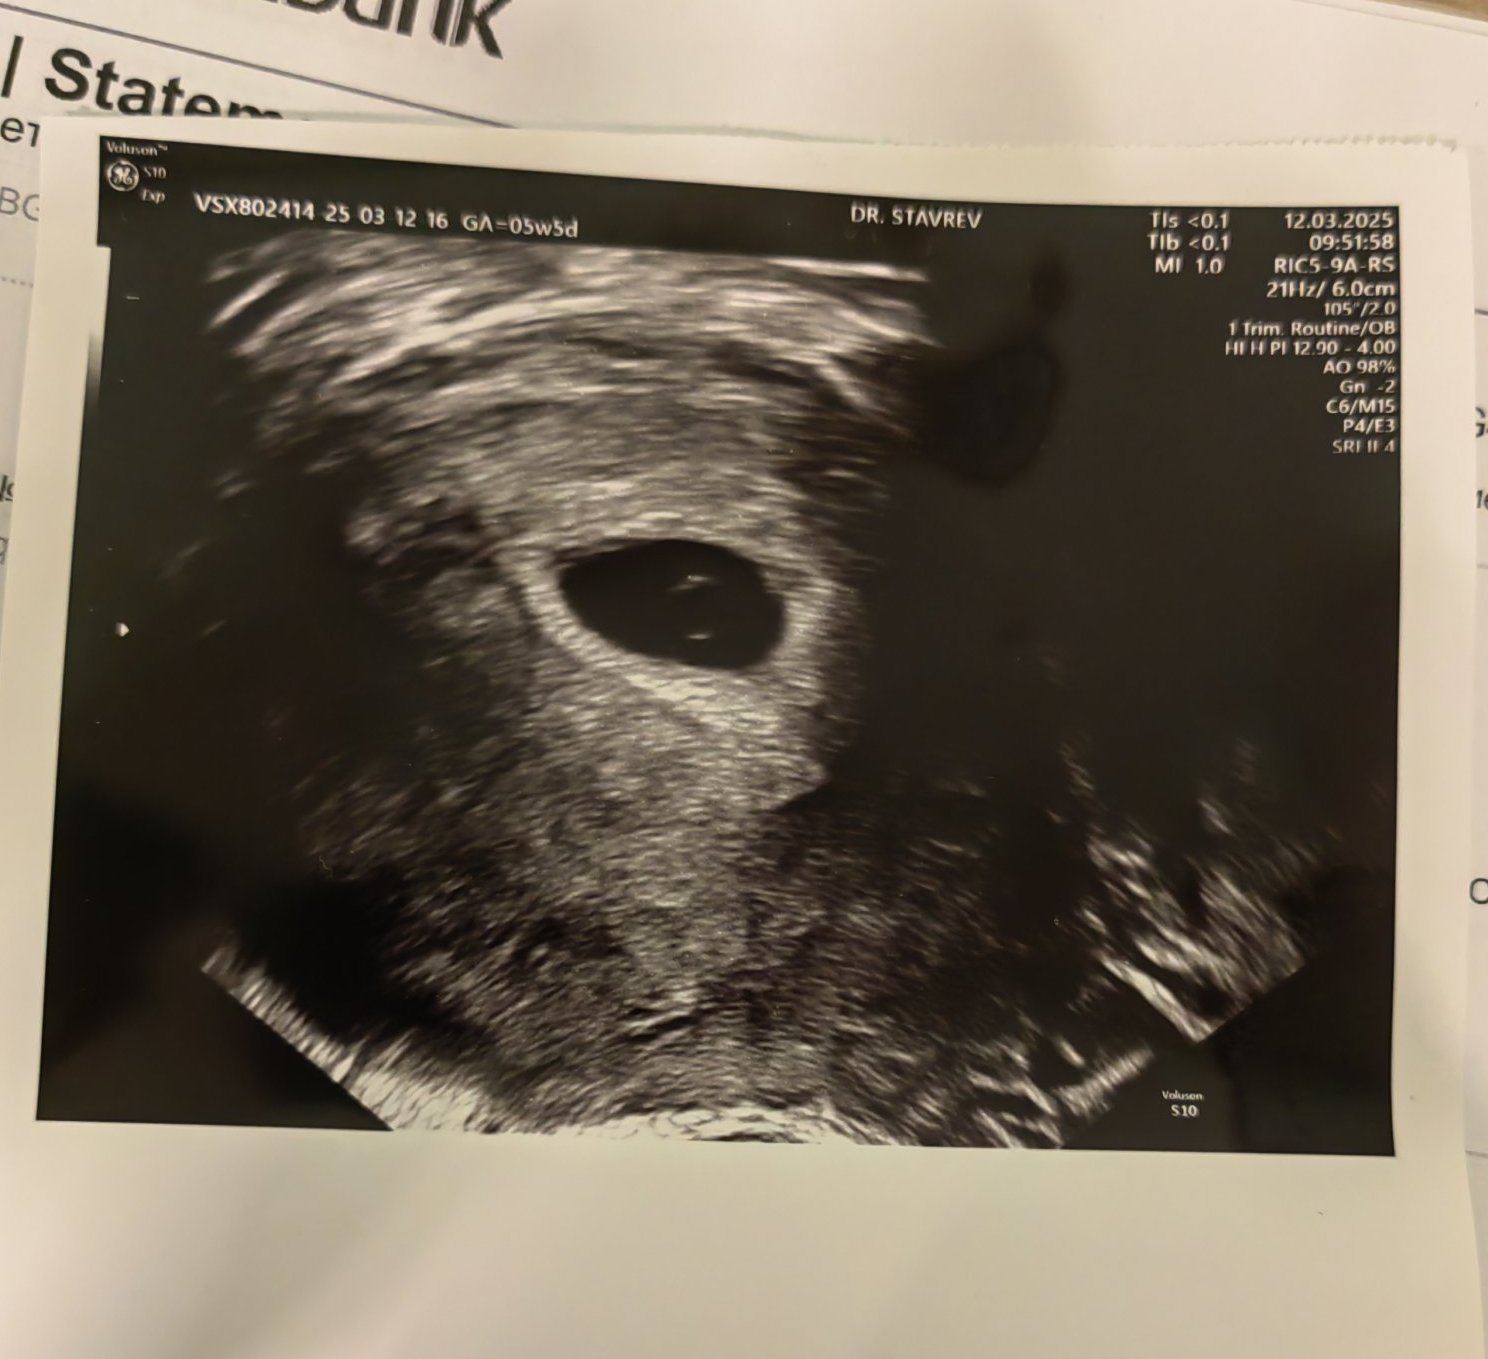

Какво представлява изображението от ехографията на 5-седмична и 2-дневна бременност?